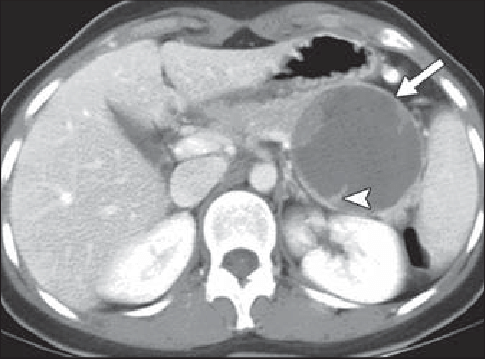

Incidentally seen liver lesion.

Isodense to liver on other phases

FNH

homogeneously hypervascular on arterial phase imaging and nearly isodense to liver on other phases; the additional presence of a central scar is essentially pathognomonic.

—> in a younger woman w/o hx of cancer, can be dx from the CT appearance

—>hemangioma would be hypervascular but isodense to vessels, not liver.